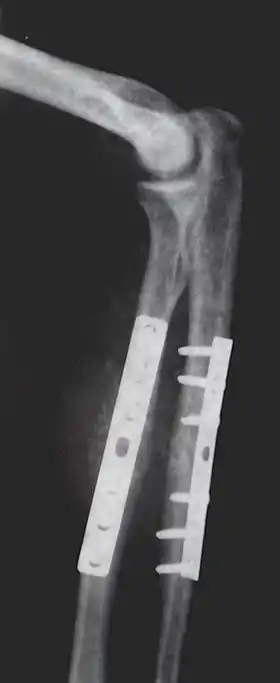

Closed Reduction Internal Fixation (CRIF) is reduction without any open surgery, followed by internal fixation. It appears to be an acceptable alternative in unstable distressed lateral condylar fractures of the humerus in children, but if fracture displacement after closed reduction exceeds 2 mm, open reduction and internal fixation is recommended.[4]

Various techniques of minimally invasive surgery for internal fixation of bones have been reported. The treatment of fractures of the distal third of the tibia has evolved with the development of improved imaging and surgical techniques.[5]